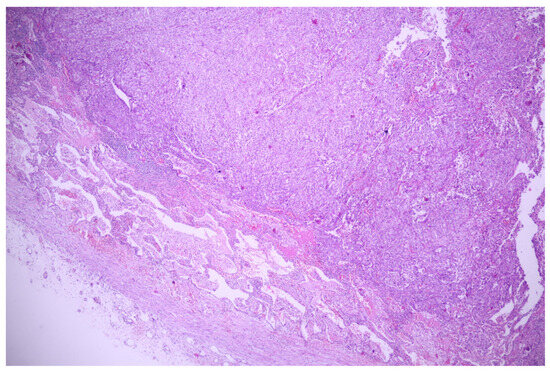

3.1. Case No. 1

3.2. Case No. 2

3.3. Case No. 3

3.4. Case No. 4

4.1.2. Lung Squamous Cell Carcinoma

4.2. Atipycal Histopathological Aspects of Common Types of Lung Cancer in Literature Review